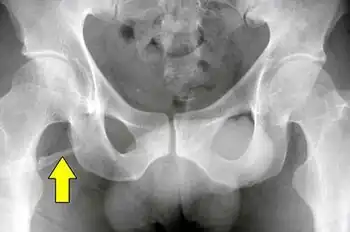

Pelvic digit

A pelvic digit, pelvic finger, or pelvic rib is a rare congenital abnormality in humans, in which bone tissue develops in the soft tissue near the pelvis, resembling a rib or finger and often divided into one or more segments with pseudo-articulations. Pelvic digits are typically benign and asymptomatic, and are usually discovered accidentally. Approximately 41 cases have been reported.[1]

The pelvic digit was first reported by D. Sullivan and W.S. Cornwell in 1974.[2] Pelvic digits may be located at any level of the pelvis, the lower ribs, or even the anterior abdominal wall. It is theorized that pelvic digit anomalies arise during the mesenchymal stage of bone growth, within the first six weeks of embryogenesis. Their formation may result from a failure of the primordium of the coccyx to fuse to the vertebral column, leading to the independent development of a proto-rib structure.[1]